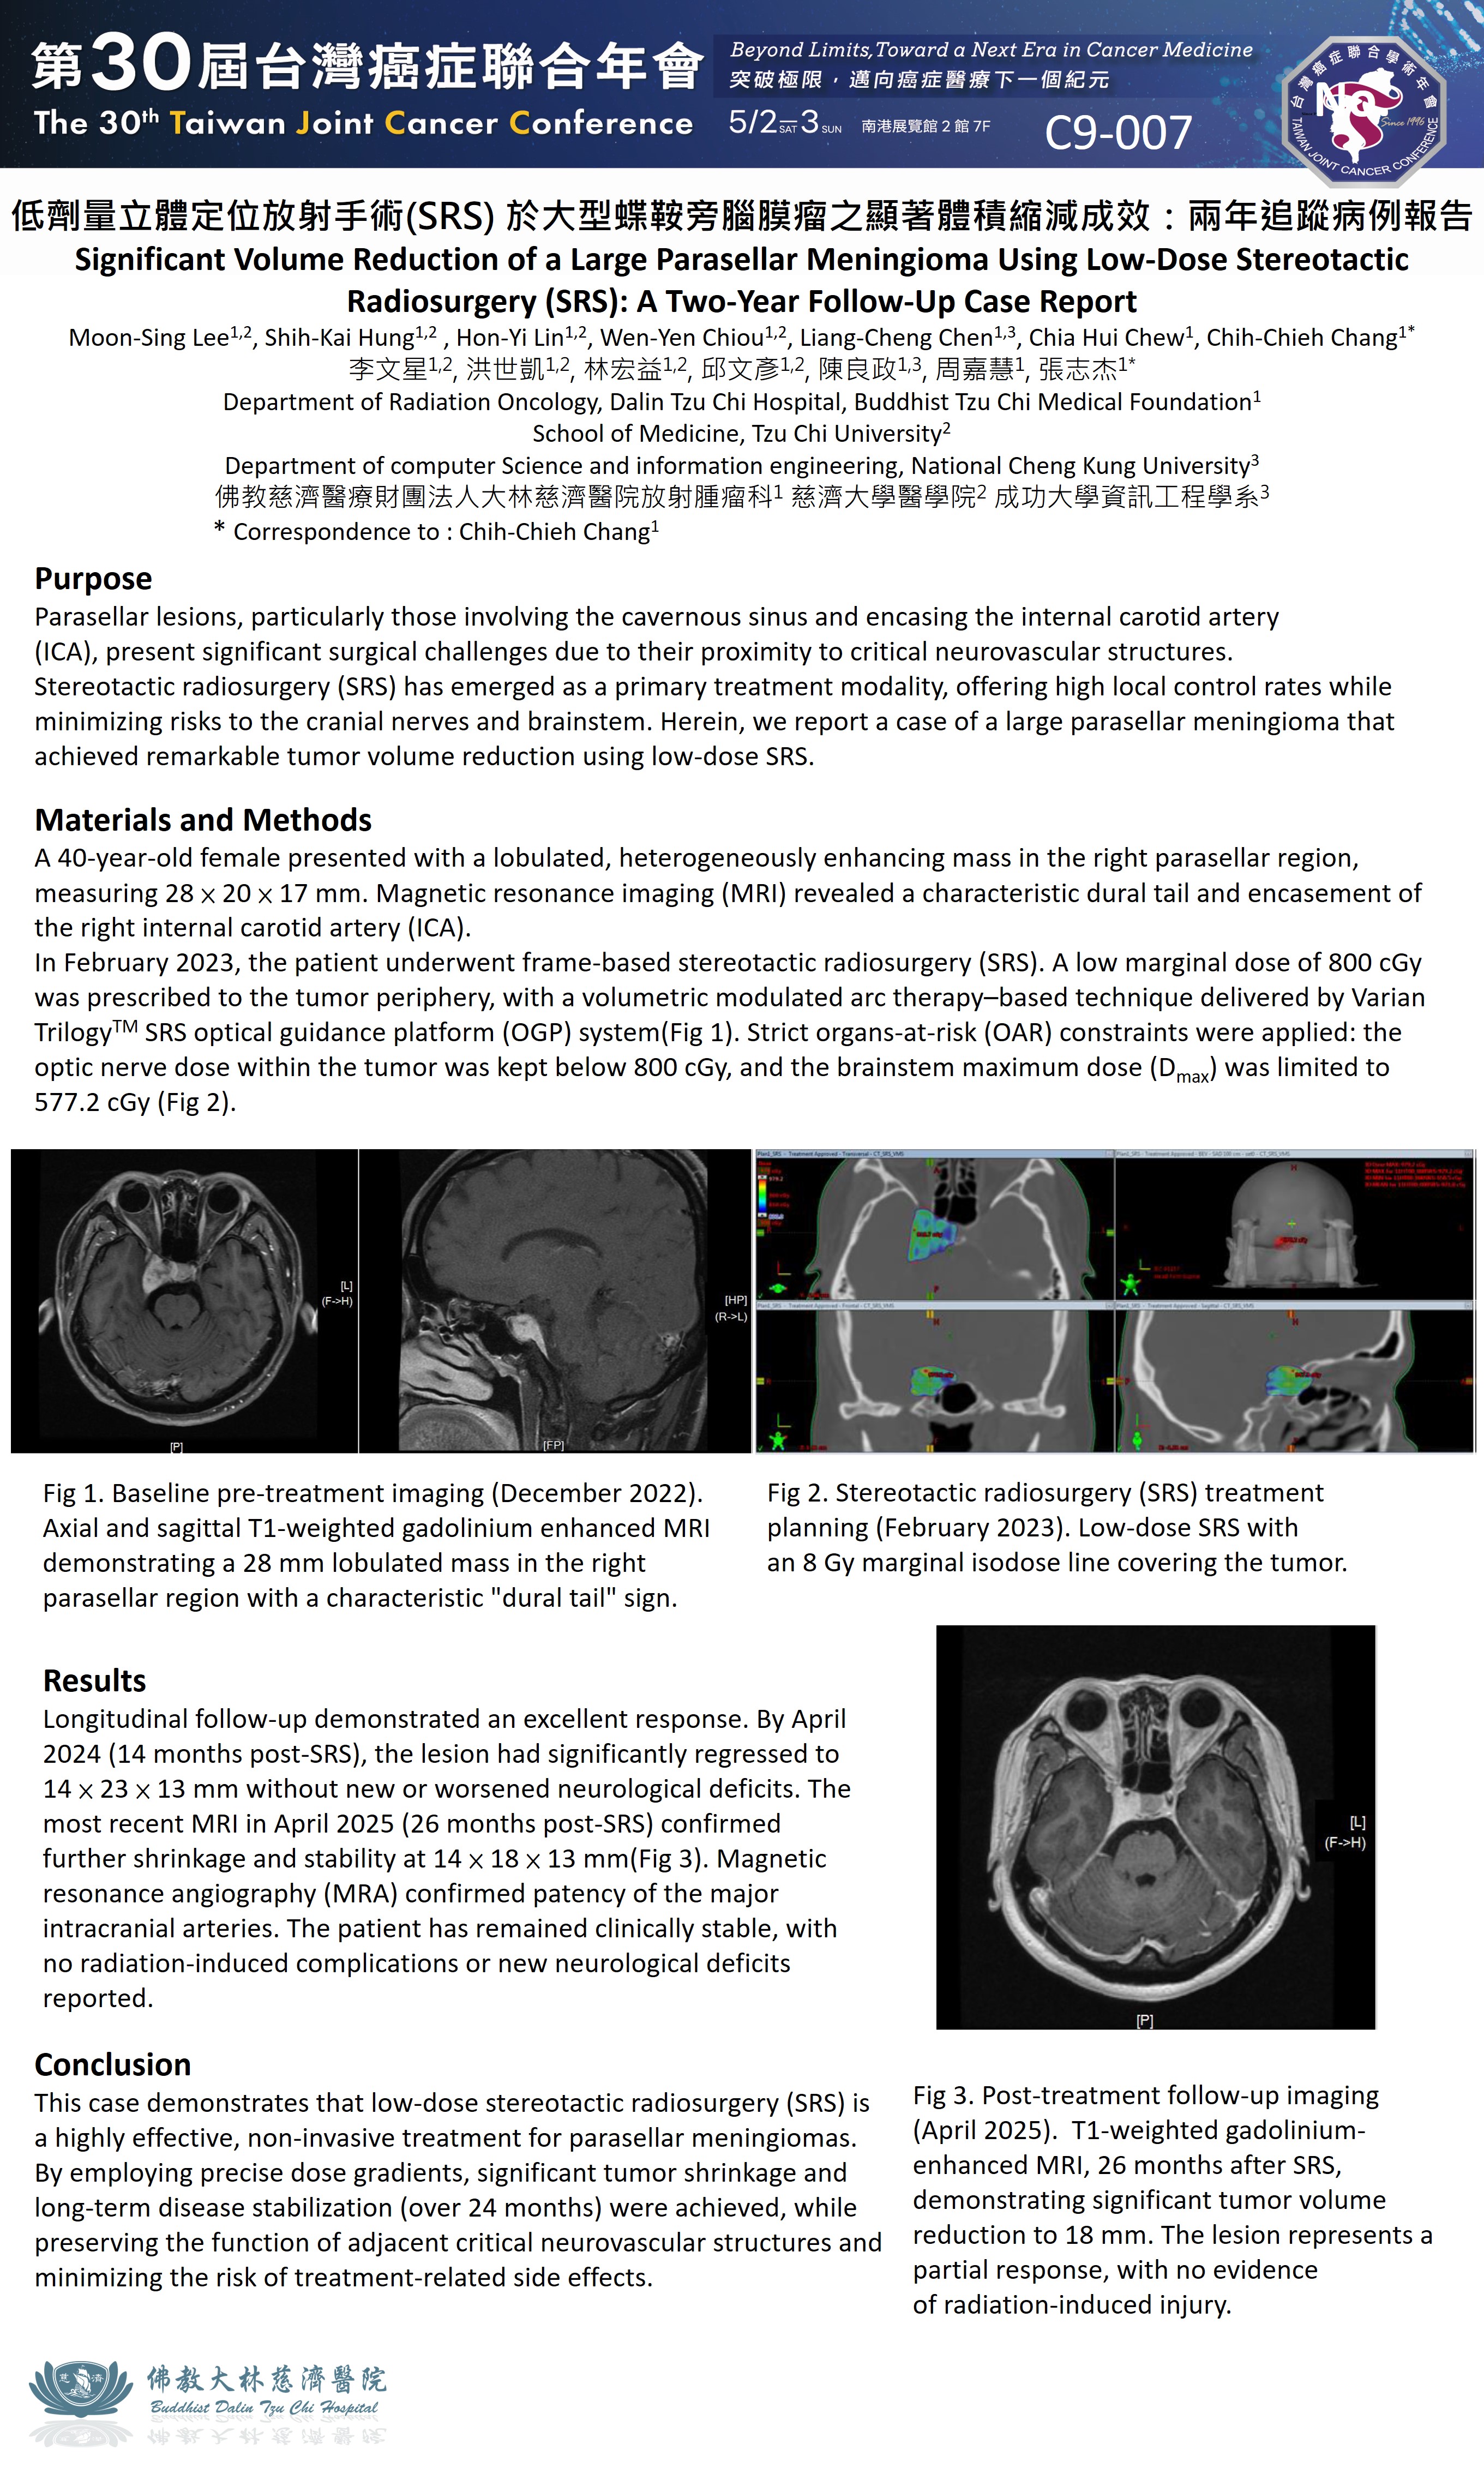

低劑量立體定位放射手術 (SRS) 於大型蝶鞍旁腦膜瘤之顯著體積縮減成效:兩年追蹤病例報告

李文星1,2, 洪世凱1,2, 林宏益1,2, 邱文彥1,2, 陳良政1,3, 周嘉慧1, 張志杰1

1 Department of Radiation Oncology, Dalin Tzu Chi Hospital, Buddhist Tzu Chi Medical Foundation

2 School of Medicine, Tzu Chi University

3 Department of computer Science and information engineering, National Cheng Kung University